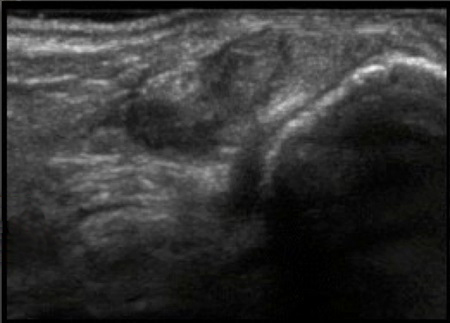

Foot & Ankle Peroneal Tendons Short Axis Image

1. Lateral Retinaculum

2. Muscle Belly

3. Peroneus Longus

4. Peroneus Brevis

5. Lateral Malleolus of the Fibula